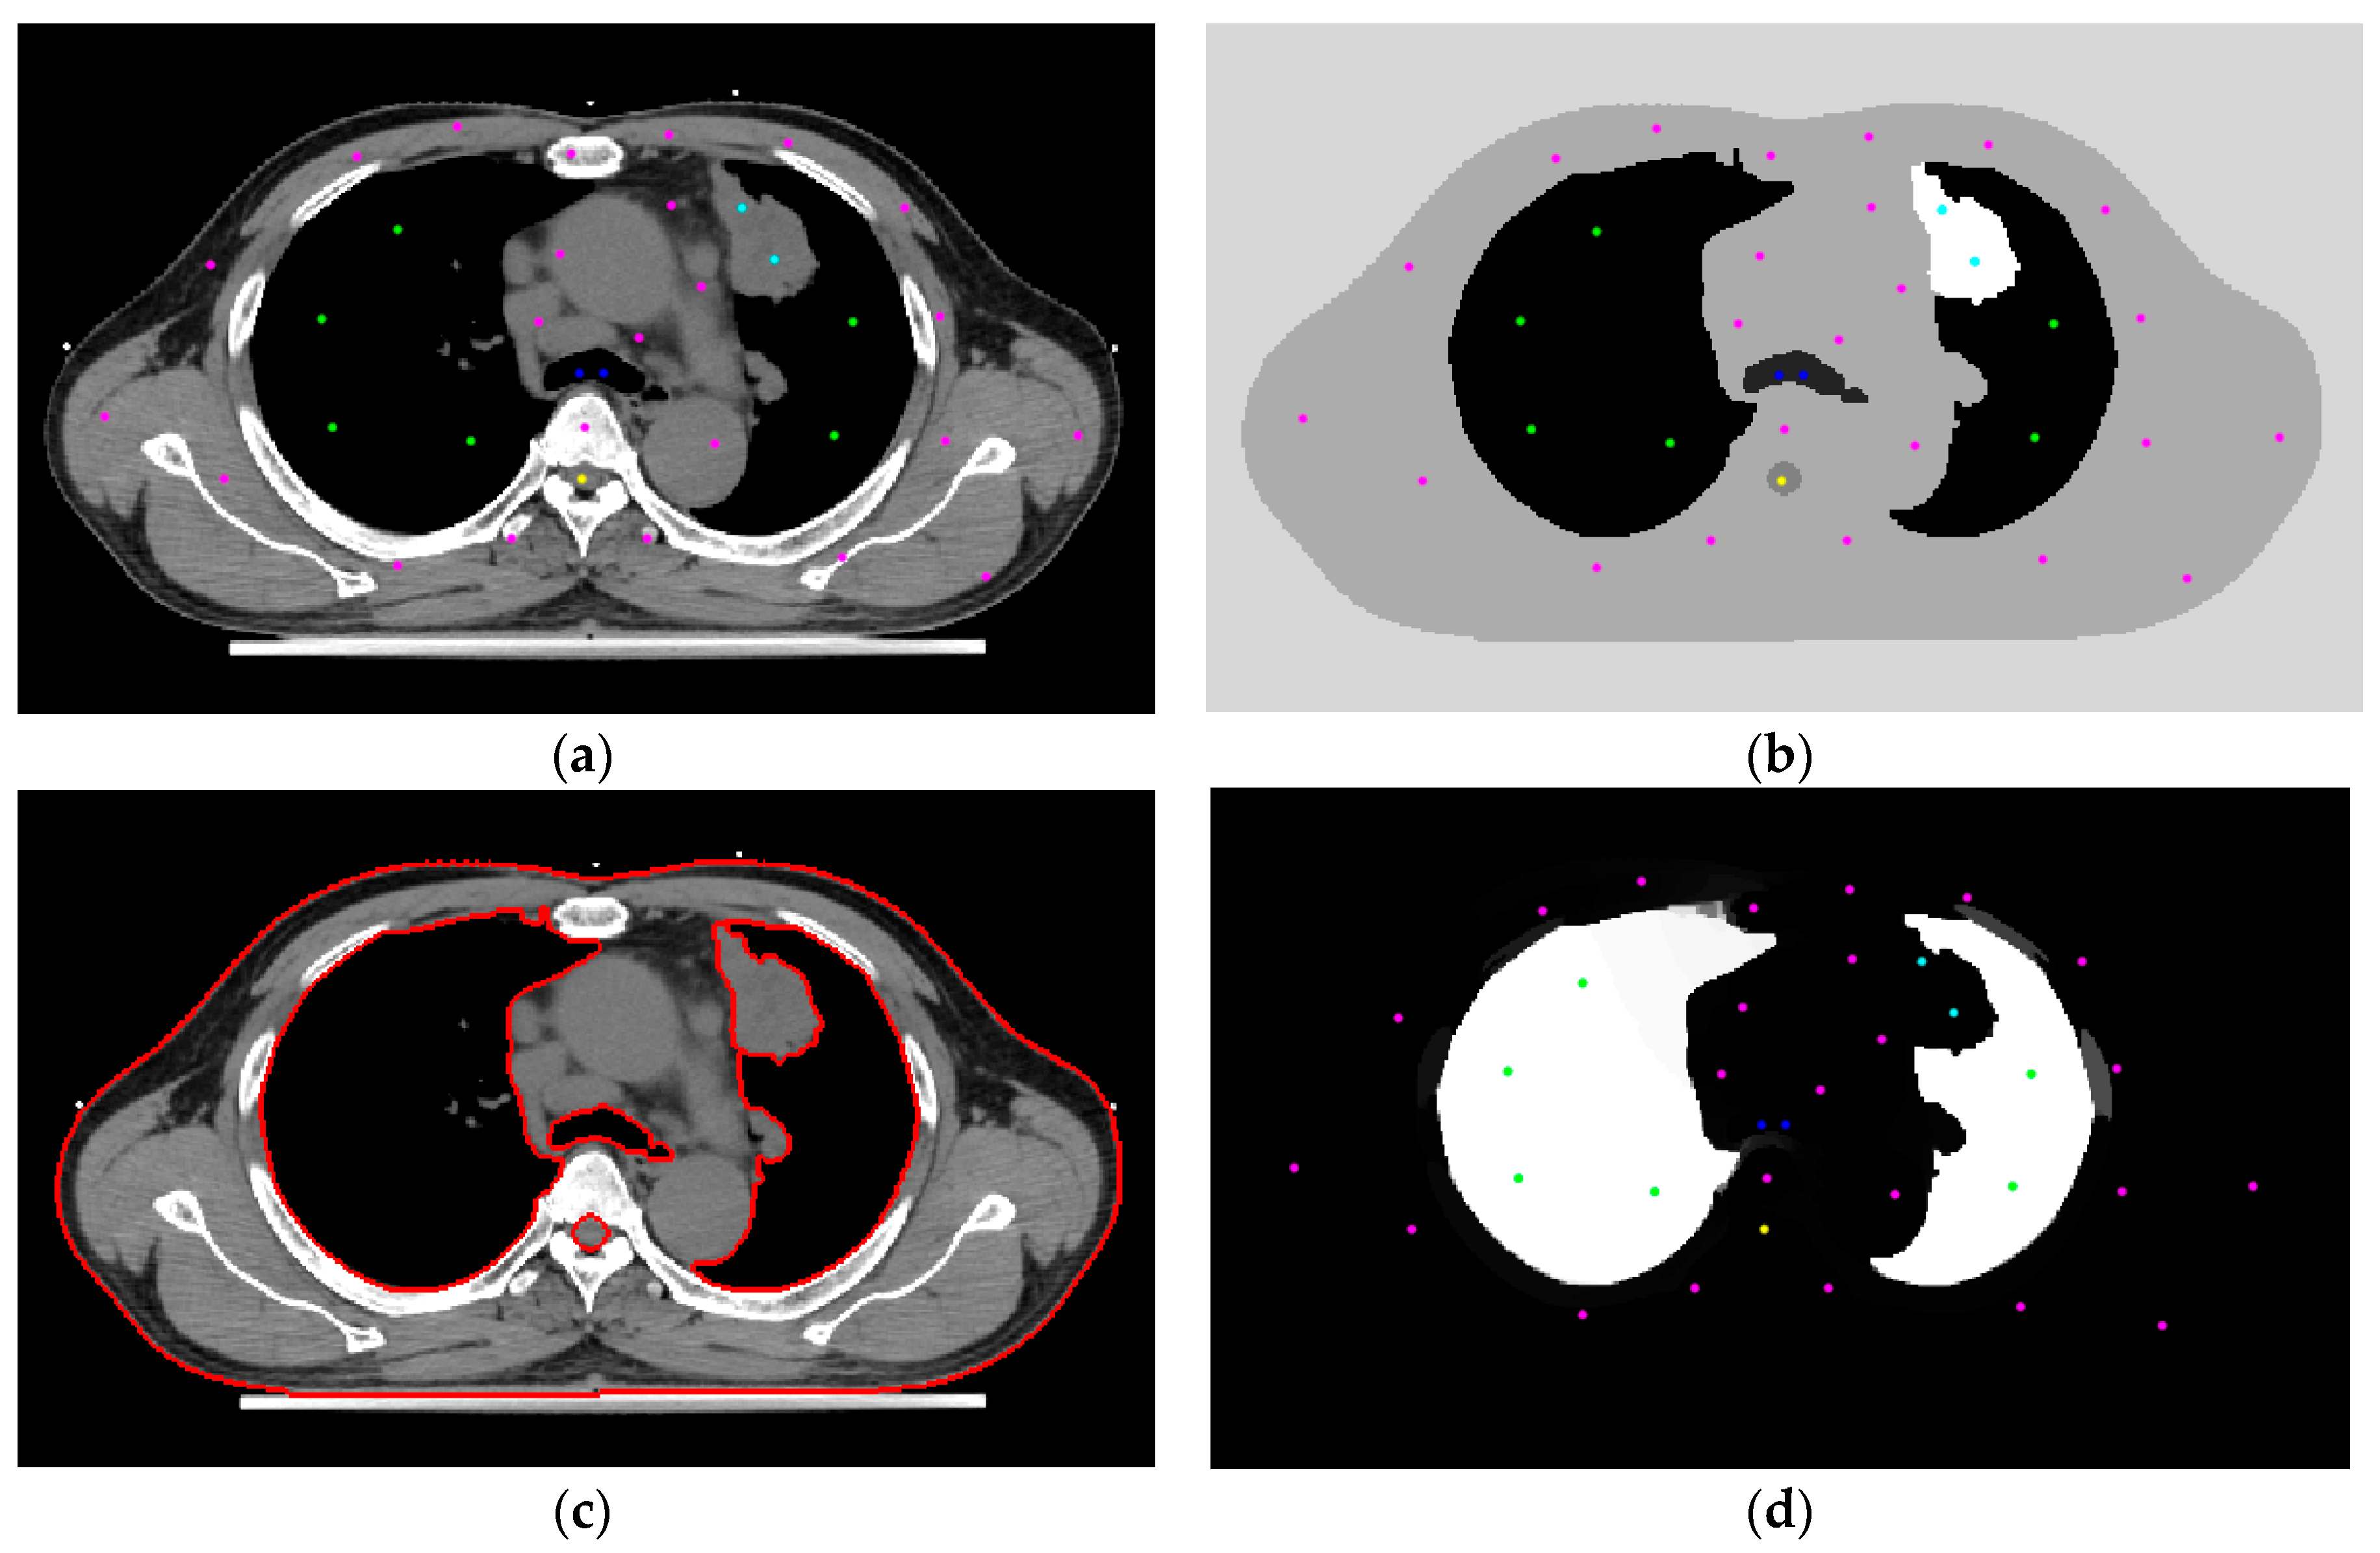

2.2. Initial Settings

2.3. Random Walks Algorithm

2.4. Boundary Erosion

2.5. Use of the Skeleton Technique to Produce Seeds

3.1. Initial Settings